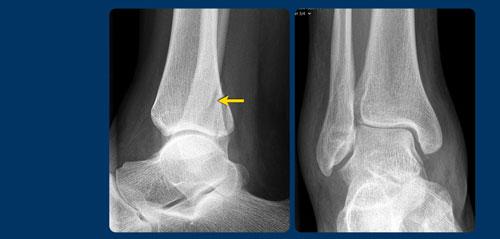

Giai đoạn 2

Trường hợp này phức tạp hơn.

Đường gãy xương mác nằm ở mức khớp chày mác xa (syndesmosis) và một số người có thể xếp loại đây là gãy Weber B, tuy nhiên hình ảnh không điển hình cho Weber B. Gãy Weber B có đường gãy chéo và nghiêng hơn do đây là gãy do lực đẩy, sẽ được thảo luận ở phần sau.

Chỉ cần quan sát hình ảnh, bạn có thể hiểu được cơ chế chấn thương (cuộn ảnh để xem).

Đây là gãy xương Weber A hai mắt cá giai đoạn 2, không ổn định.

Hình bên trái là một ví dụ khác về gãy xương hai mắt cá không ổn định giai đoạn 2 Weber A.

Hình bên phải cho thấy đường gãy thẳng đứng của mắt cá trong (mũi tên). Đây luôn là giai đoạn 2 và không ổn định. Điều này có nghĩa là giai đoạn 1 đã xảy ra trước đó, vì cơ chế chấn thương luôn tuân theo trình tự nghiêm ngặt: giai đoạn 1 trước, sau đó mới đến giai đoạn 2.

Vòng ổn định bị phá vỡ ở hai vị trí (cuộn ảnh để xem).